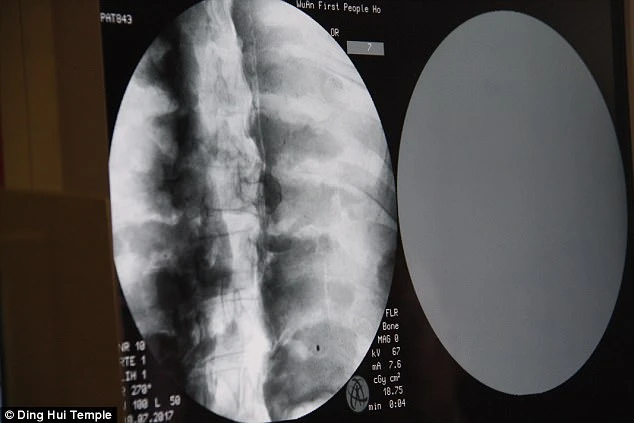

Sự kiện gây chấn động diễn ra vào ngày 8 tháng 7 năm 2017, khi các nhà khoa học tiến hành chụp CT để kiểm tra bên trong “bức tượng” này trước sự chứng kiến của giới truyền thông và đông đảo người dân. Kết quả hình ảnh quét được đã khiến tất cả những người có mặt phải bàng hoàng. Các bác sĩ xác nhận rằng bên dưới lớp mạ vàng, nhà sư Ci Xian vẫn giữ được bộ xương nguyên vẹn cùng một bộ não hoàn chỉnh.

Kết quả hình ảnh từ máy quét đã khiến toàn bộ giới khoa học và những người chứng kiến phải kinh ngạc đến mức sững sờ. Các bác sĩ xác nhận rằng nhà sư Ci Xian vẫn còn giữ được một bộ xương hoàn chỉnh cùng một bộ não nguyên vẹn.

Bác sĩ Wu Yongqing, người trực tiếp tham gia buổi kiểm tra cho biết xương của ngài khỏe mạnh và rõ ràng như một người bình thường. Từ xương hàm trên, răng, xương sườn, xương sống cho đến tất cả các khớp đều vẫn còn nguyên vẹn một cách khó tin. Sự tồn tại hoàn hảo của thi hài sau hơn 1.000 năm đã chứng minh kỹ thuật ướp xác đỉnh cao thời bấy giờ, tạo nên một hiện tượng chấn động khiến cả thế giới phải chú ý.

Những hình ảnh có được sau khi chụp CT